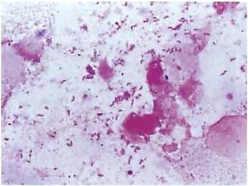

入院患者の喀痰です。

何がいるかわかりますか…?

答えはワタシデス!!バイオフィルム形成ちゅう♪

培養からはムコイド型の緑膿菌が検出されました。患者の気道内にバイオフィルムを形成した緑膿菌は粘性物質で菌体を包んで定着し、塗抹ではカエルの卵状に見え、培養ではM型集落が検出されます。